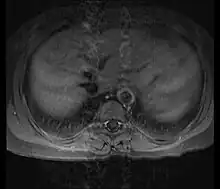

Although the cause of Takayasu arteritis is unknown, the condition is characterized by segmental and patchy granulomatous inflammation of the aorta and its major derivative branches. This inflammation leads to arterial stenosis, thrombosis, and aneurysms.[4] There is irregular fibrosis of the blood vessels due to chronic vasculitis, leading to sometimes massive intimal fibrosis (fibrosis of the inner section of the blood vessels).[6] Prominent narrowing due to inflammation, granuloma, and fibrosis is often seen in arterial studies such as magnetic resonance angiography (MRA), computed tomography angiography (CTA), or arterial angiography (DSA).